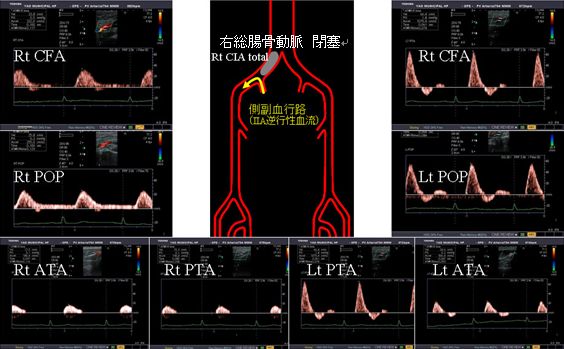

下肢動脈エコー

下肢動脈エコーでは腹部から足首の動脈をドップラーなど用いて評価し、動脈閉塞および狭窄の有無を詳細に診断する検査です。最近、動脈硬化性疾患の急増に伴い閉塞性動脈硬化症が増加していますが、日常診断における未診断、未治療が指摘されています。歩行による下肢の痺れや痛みがある場合には下肢動脈エコーを施行することが望ましいと思われます。検査時間は20分~40分程度です。